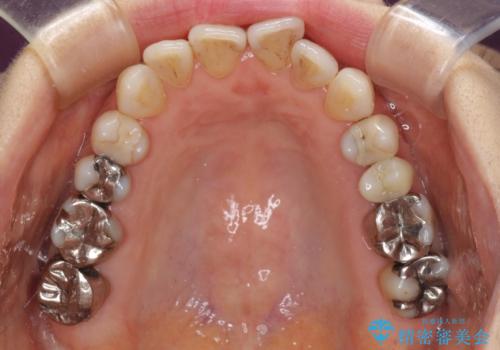

- 前歯の上下スペースと前歯の隙間を気にして来院された患者様です。

インビザラインにより上下の前歯の隙間を閉じながら、IPRを用いて口元の突出感を合わせて改善していくこととしました。

上下の隙間に舌が入り込むことが、すきっ歯やオープンバイトの原因であったため、舌の筋肉のトレーニングも並行して行い、後戻りの抑制を図りました。